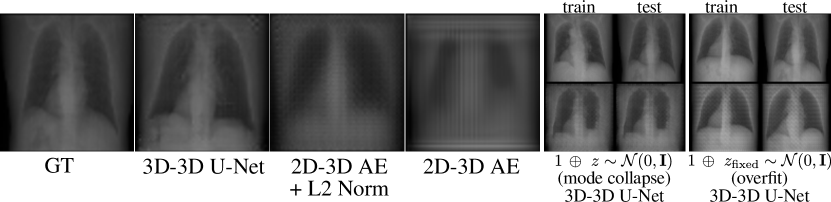

Refer to caption

Figure 3: Effect of reformulating 2D-3D mapping into 3D-3D.

Mapping reformulation

In Figure 3, we present results from initial experiments comparing an asymmetrical 2D to 3D strategy versus our reformulation as a 3D to 3D mapping. The 2D to 3D approach involves aggregating the individual encoded 2D view features, which serve as input to a 3D decoder. However, this results in highly blurred outputs due to the information content loss from the latent encoding. Despite the simplicitiy of such an approach in terms of feature alignment, important fine-grained details are missing. In contrast, our approach reformulates the problem into a 3D to 3D mapping in a simple architecture, achieving high-fidelity image translations even when using a single input view. We ablate our ’repeat and concatenate’ preprocessing pipeline by instead concatenating noise sampled from a normal distribution. When the vector 𝒛𝒛\boldsymbol{z} is fixed for each patient, the model causes overfitting, while gathering a new 𝒛𝒛\boldsymbol{z} for each iteration results in mode collapsing, where it produces the same output irrespective of the input.